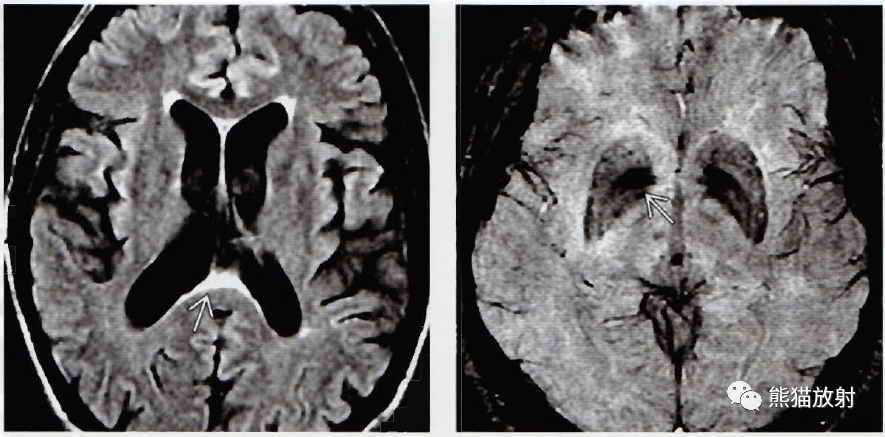

什么是「脑萎缩改变」,如何与硬膜下积液相鉴别?

并发脑萎缩的老年正常压力脑积水步态不稳走路前冲不能控制不倒翁样

前几日遇到的一例神经病例,脑内脑外?初步考虑什么? [病例帖]